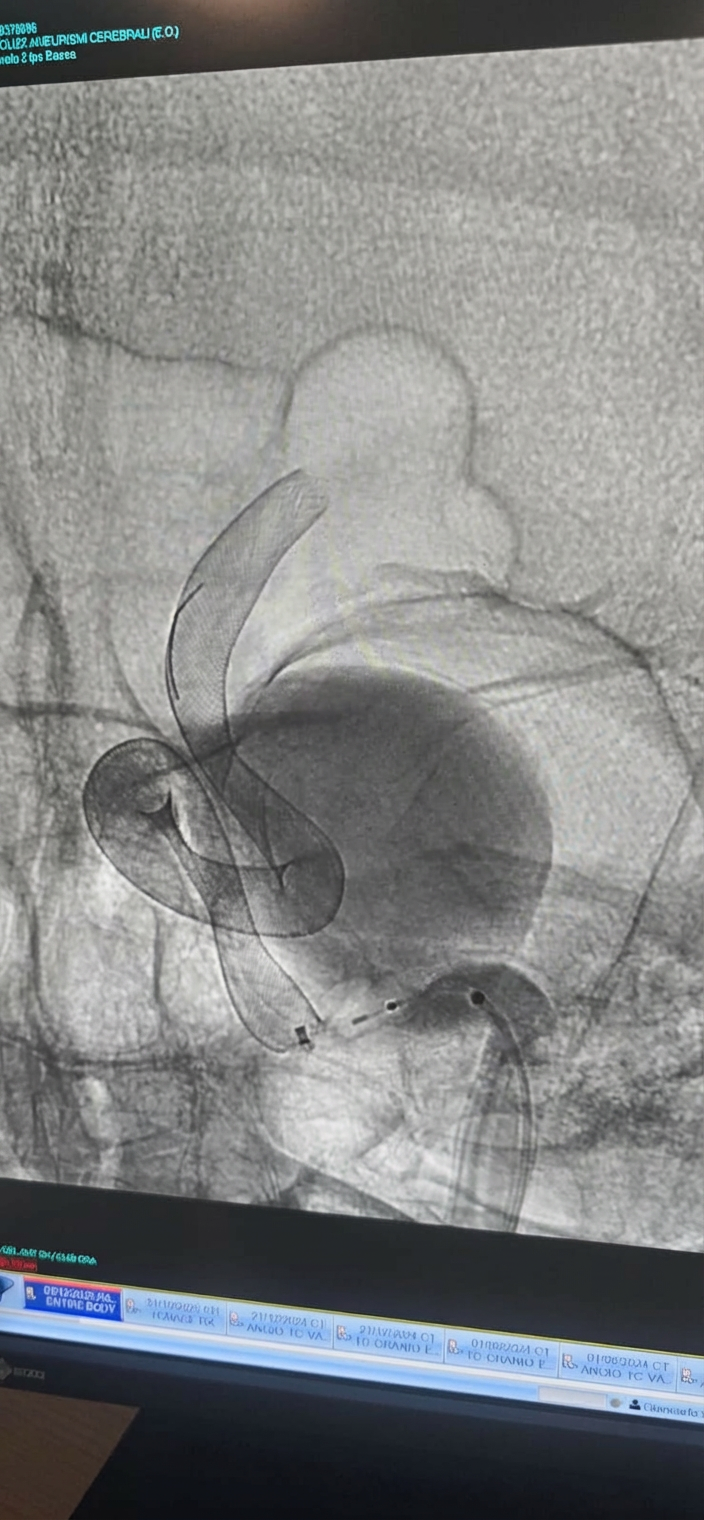

Procedure endovascolari e percutanee:

• Angiografia cerebrale diagnostica

• Embolizzazione di aneurismi e malformazioni vascolari

• Trattamento endovascolare stenosi carotidea

• Embolizzazione ematomi subdurali cronici

• Vertebroplastica e cifoplastica

• Trattamento percutaneo ernie del disco